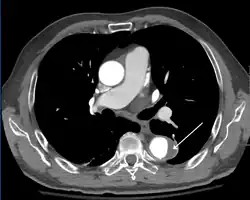

Computed tomography

Computed tomography angiography is a fast, non-invasive test that gives an accurate three-dimensional view of the aorta. These images are produced by taking rapid, thin-cut slices of the chest and abdomen, and combining them in the computer to create cross-sectional slices. To delineate the aorta to the accuracy necessary to make the proper diagnosis, an iodinated contrast material is injected into a peripheral vein. Contrast is injected and the scan performed using a bolus tracking method. This type of scan is timed to injection to capture the contrast as it enters the aorta. The scan then follows the contrast as it flows through the vessel. It has a sensitivity of 96 to 100% and a specificity of 96 to 100%. Disadvantages include the need for iodinated contrast material and the inability to diagnose the site of the intimal tear.

-

CT with contrast demonstrating aneurysmal dilation and a dissection of the ascending aorta (type A Stanford) -

Chest CT with descending (type B Stanford) aortic dissection (red circle)

Type A dissection with pericardial effusion as a result.